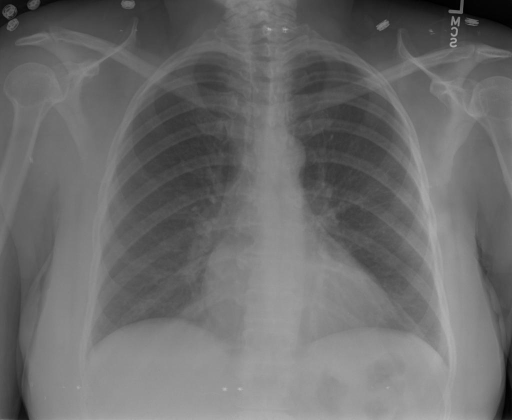

## 本文贡献  - 借助ChatGPT以及公开的数据集,我们构造了一个`X光影像-诊断报告`对的医学多模态数据集; - 我们将构建的中文胸部X光片诊断数据集在[VisualGLM-6B](https://github.com/THUDM/VisualGLM-6B)进行微调训练,并开放了部分训练权重用于学术研究; ## 数据集 - [MIMIC-CXR](https://physionet.org/content/mimic-cxr-jpg/2.0.0/)是一个公开可用的胸部X光片数据集,包括377,110张图像和227,827个相关报告。 - [OpenI](https://openi.nlm.nih.gov/faq#collection)是一个来自印第安纳大学医院的胸部X光片数据集,包括6,459张图像和3,955个报告。 在上述工作中,报告信息都为非结构化的,不利于科学研究。为了生成合理的医学报告,我们对两个数据集进行了预处理,并最终得到了可以用于训练的**英文报告**。除此之外,为了更好的支持中文社区发展,借助ChatGPT的能力,我们将英文报告进行了中文翻译,并最终形成了可用于训练的数据集。 |数据集|数量|下载链接| |:-|:-|:-| |MIMIC-CXR-zh|-|-| |OpenI-zh|6,423|[诊疗报告(英文)](./data/openi-en.json)、[诊疗报告(中文)](./data/Xray/openi-zh.json) 、[X光影像](https://pan.baidu.com/s/13GBsDMKf6xBZBSHpoWH_EA?pwd=k9sh)| ## 快速上手 1. 安装环境 ```bash # 安装依赖 pip install -r requirements.txt # 国内换源安装依赖 pip install -i https://mirrors.aliyun.com/pypi/simple/ -r requirements.txt ``` 此时默认会安装`deepspeed`库(支持`sat`库训练),此库对于模型推理并非必要,同时部分`Windows`环境安装此库时会遇到问题。 如果想绕过`deepspeed`安装,我们可以将命令改为: ```bash # 安装依赖 pip install -i https://mirrors.aliyun.com/pypi/simple/ -r requirements_wo_ds.txt # 安装SwissArmyTransformer pip install -i https://mirrors.aliyun.com/pypi/simple/ --no-deps "SwissArmyTransformer>=0.3.6" ``` 2. 模型推理 CLI推理: ```python python cli_demo.py --from_pretrained checkpoints/finetune-XrayGLM-05-25-01-04 --prompt_zh '详细描述这张胸部X光片的诊断结果' ``` 更多[参数](https://github.com/WangRongsheng/XrayGLM/blob/main/cli_demo.py#L16) ## 效果展示 影像诊断: |X光影像|诊疗报告(医生)|XrayGLM| |:-|:-|:-| ||根据X射线图像,心脏大小正常,肺部看起来很清晰。已经排除了肺炎、积液、水肿、气胸、腺病、结节或肿块的存在。该发现表明一切正常。换句话说,总体印象是胸部正常。|X光片显示,心脏大小正常。肺部没有气胸或胸腔积液的证据。骨骼结构看起来没有任何异常。总的来说,X光片表明没有发现急性心肺疾病的迹象。| ||X光图片显示没有扭曲的区域、可疑的骨质不透明度或胸腺积液。心脏大小轻微增大,但非常稳定。此外,没有气胸的证据,肺野也正常。总体来说,X光片显示没有急性心脏异常,但要注意轻微的心脏扩大。|X光片显示,心脏大小正常。肺部和纵隔轮廓清晰,没有气胸或胸腔积液的证据。骨骼结构完整,没有任何急性异常。| ||心影形态在正常范围内。没有急性骨质异常。有可能出现没有明显的吸水或肺实质状况的线索。没有大面积积液或气胸。有可能怀疑其有误吸或肺实质问题。为了确诊和治疗,可能需要进行适当的影像学随访。|心脏大小正常,肺部和纵隔轮廓清晰。没有急性异常或活动受限的证据。没有任何明显的气胸、胸腔积液或肺不张的迹象。此外,也没有发现任何局灶性骨质异常或其他急性疾病。| 多轮对话: |X光影像|诊疗报告(医生)| |:-|:-| ||右侧主动脉突出观察到。心脏大小正常。胸部未发现明显的肺气肿、胸膜积液或可疑的肺部病变。报告指出已知右侧主动脉情况正常。| ```bash >> X光影像路径:./data/Xray/861_1.png >> 用户:这是一张什么图? >> XrayGLM:这张图片显示的是一张肺部检查的X光片。 >> 用户:请描述这张胸部X光片的诊断结果 >> XrayGLM:心脏大小正常,肺部清晰。没有急性心肺疾病的证据。 >> 用户:是否存在肺气肿? >> XrayGLM:没有肺气肿。心脏大小正常,肺部清晰。没有发现急性心肺疾病的证据。 >> 用户:平时饮食该注意什么? >> XrayGLM:饮食应该健康,均衡。建议增加蛋白质的摄入量,因为蛋白质有助于维持肌肉和骨骼的健康。多食用蔬菜、水果、全谷物以及健康的脂肪来源如橄榄油、鱼类等可以帮助获得足够的维生素和矿物质。此外,避免过度饮酒或吸烟,这些习惯可能会对心脏健康产生负面影响。 ``` ## 未来展望 1. 模型的能力更多来源于数据的支持,`OpenI-zh`作为微调数据集,其数据量足以支持研究,在更广泛的任务和性能表现上,我们认为**在大规模数据集上预训练并在高质量少量数据集上微调是一种可行的方案**; 2. 普遍意义的理解上,视觉多模态模型=视觉模型+语言模型。除了需要关注视觉模型信息与语言模型输出的搭配外,还需要**额外关注到语言模型的加强,在人机的对话中,尤其是医疗语言模型的问答上,除了专业的医疗问题回答,带有人文情怀的有温度的回答更应该是我们追寻的目标**。 ## 项目致谢 1. [VisualGLM-6B](https://github.com/THUDM/VisualGLM-6B)为我们提供了基础的代码参考和实现; 2. [MiniGPT-4](https://github.com/Vision-CAIR/MiniGPT-4)为我们这个项目提供了研发思路; 3. ChatGPT生成了高质量的中文版X光检查报告以支持XrayGLM训练; 4. [gpt_academic](https://github.com/binary-husky/gpt_academic)为文档翻译提供了多线程加速; 5. [MedCLIP](https://github.com/RyanWangZf/MedCLIP) 、[BLIP2](https://huggingface.co/docs/transformers/main/model_doc/blip-2) 、[XrayGPT](https://github.com/mbzuai-oryx/XrayGPT) 等工作也有重大的参考意义;  这项工作由[澳门理工大学应用科学学院](https://www.mpu.edu.mo/esca/zh/index.php)硕士生[王荣胜](https://github.com/WangRongsheng) 、[段耀菲](https://github.com/IsBaSO4) 、[李俊蓉](https://github.com/lijunrong0815)完成,指导老师为檀韬副教授、[彭祥佑](http://www.patrickpang.net/)老师。 *特别鸣谢:[USTC-PhD Yongle Luo](https://github.com/kaixindelele) 提供了有3000美金的OpenAI账号,帮助我们完成大量的X光报告翻译工作 ## 免责声明 本项目相关资源仅供学术研究之用,严禁用于商业用途。使用涉及第三方代码的部分时,请严格遵循相应的开源协议。模型生成的内容受模型计算、随机性和量化精度损失等因素影响,本项目无法对其准确性作出保证。即使本项目模型输出符合医学事实,也不能被用作实际医学诊断的依据。对于模型输出的任何内容,本项目不承担任何法律责任,亦不对因使用相关资源和输出结果而可能产生的任何损失承担责任。 ## 项目引用 如果你使用了本项目的模型,数据或者代码,请声明引用: ```bash @misc{wang2023XrayGLM, title={XrayGLM: The first Chinese Medical Multimodal Model that Chest Radiographs Summarization}, author={Rongsheng Wang, Yaofei Duan, Junrong Li, Patrick Pang and Tao Tan}, year={2023}, publisher = {GitHub}, journal = {GitHub repository}, howpublished = {\url{https://github.com/WangRongsheng/XrayGLM}}, } ``` ## 使用许可 此存储库遵循[CC BY-NC-SA](https://creativecommons.org/licenses/by-nc-sa/4.0/) ,请参阅许可条款。